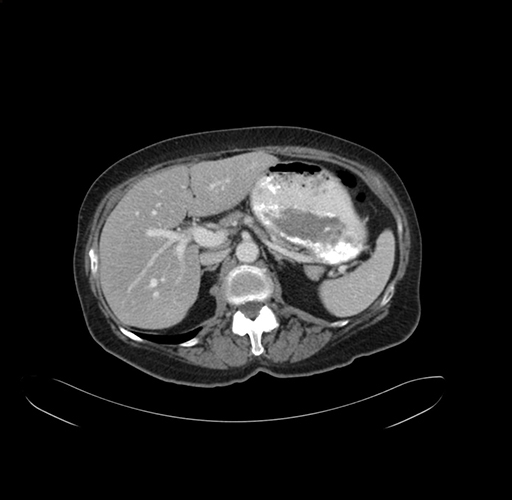

Pre-Chemo: Axial Venous

Axial Venous

Based on your CT findings, which issue(s) would give reason for "planned slowing down moment(s)" in this case?

Considering a standard right hepatectomy procedure, what step(s) of the operation would you do differently in this case?